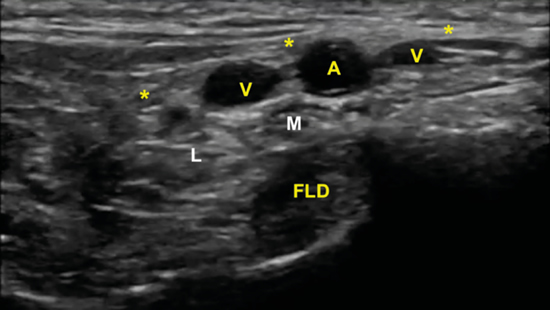

Figura 11. Imagen sonográfica de la diferenciación del nervio plantar medial (M) y del nervio plantar lateral (L) debajo de la arteria y venas (A, V) y sobre el tendón flexor largo del primer dedo (FLD). En superficie el retináculo flexor (*).

No obstante, la visualización de los nervios plantar medial y plantar lateral es más evidente cuando se avanza hacia distal. Para ello se mantiene la sonda en eje corto (Figura 13) tomando como referencia la tuberosidad posterior del calcáneo, de donde parten el eje de Dellon-Mackinnon4 y el triángulo de Heimkes (área entre tuberosidad del calcáneo, el vértice del maléolo medial y el navicular)8 (Figura 12).

La imagen sonográfica se centrará en el espacio situado bajo la fascia profunda del músculo abductor del primer dedo, por donde discurrirán los haces neurovasculares plantar medial y plantar lateral, diferenciados y separados por el septo de Heimkes o interfascicular3. El nervio plantar medial se muestra con mayor sección que el nervio plantar lateral, y las venas laterales con mayor luz que las mediales (Figura 14).